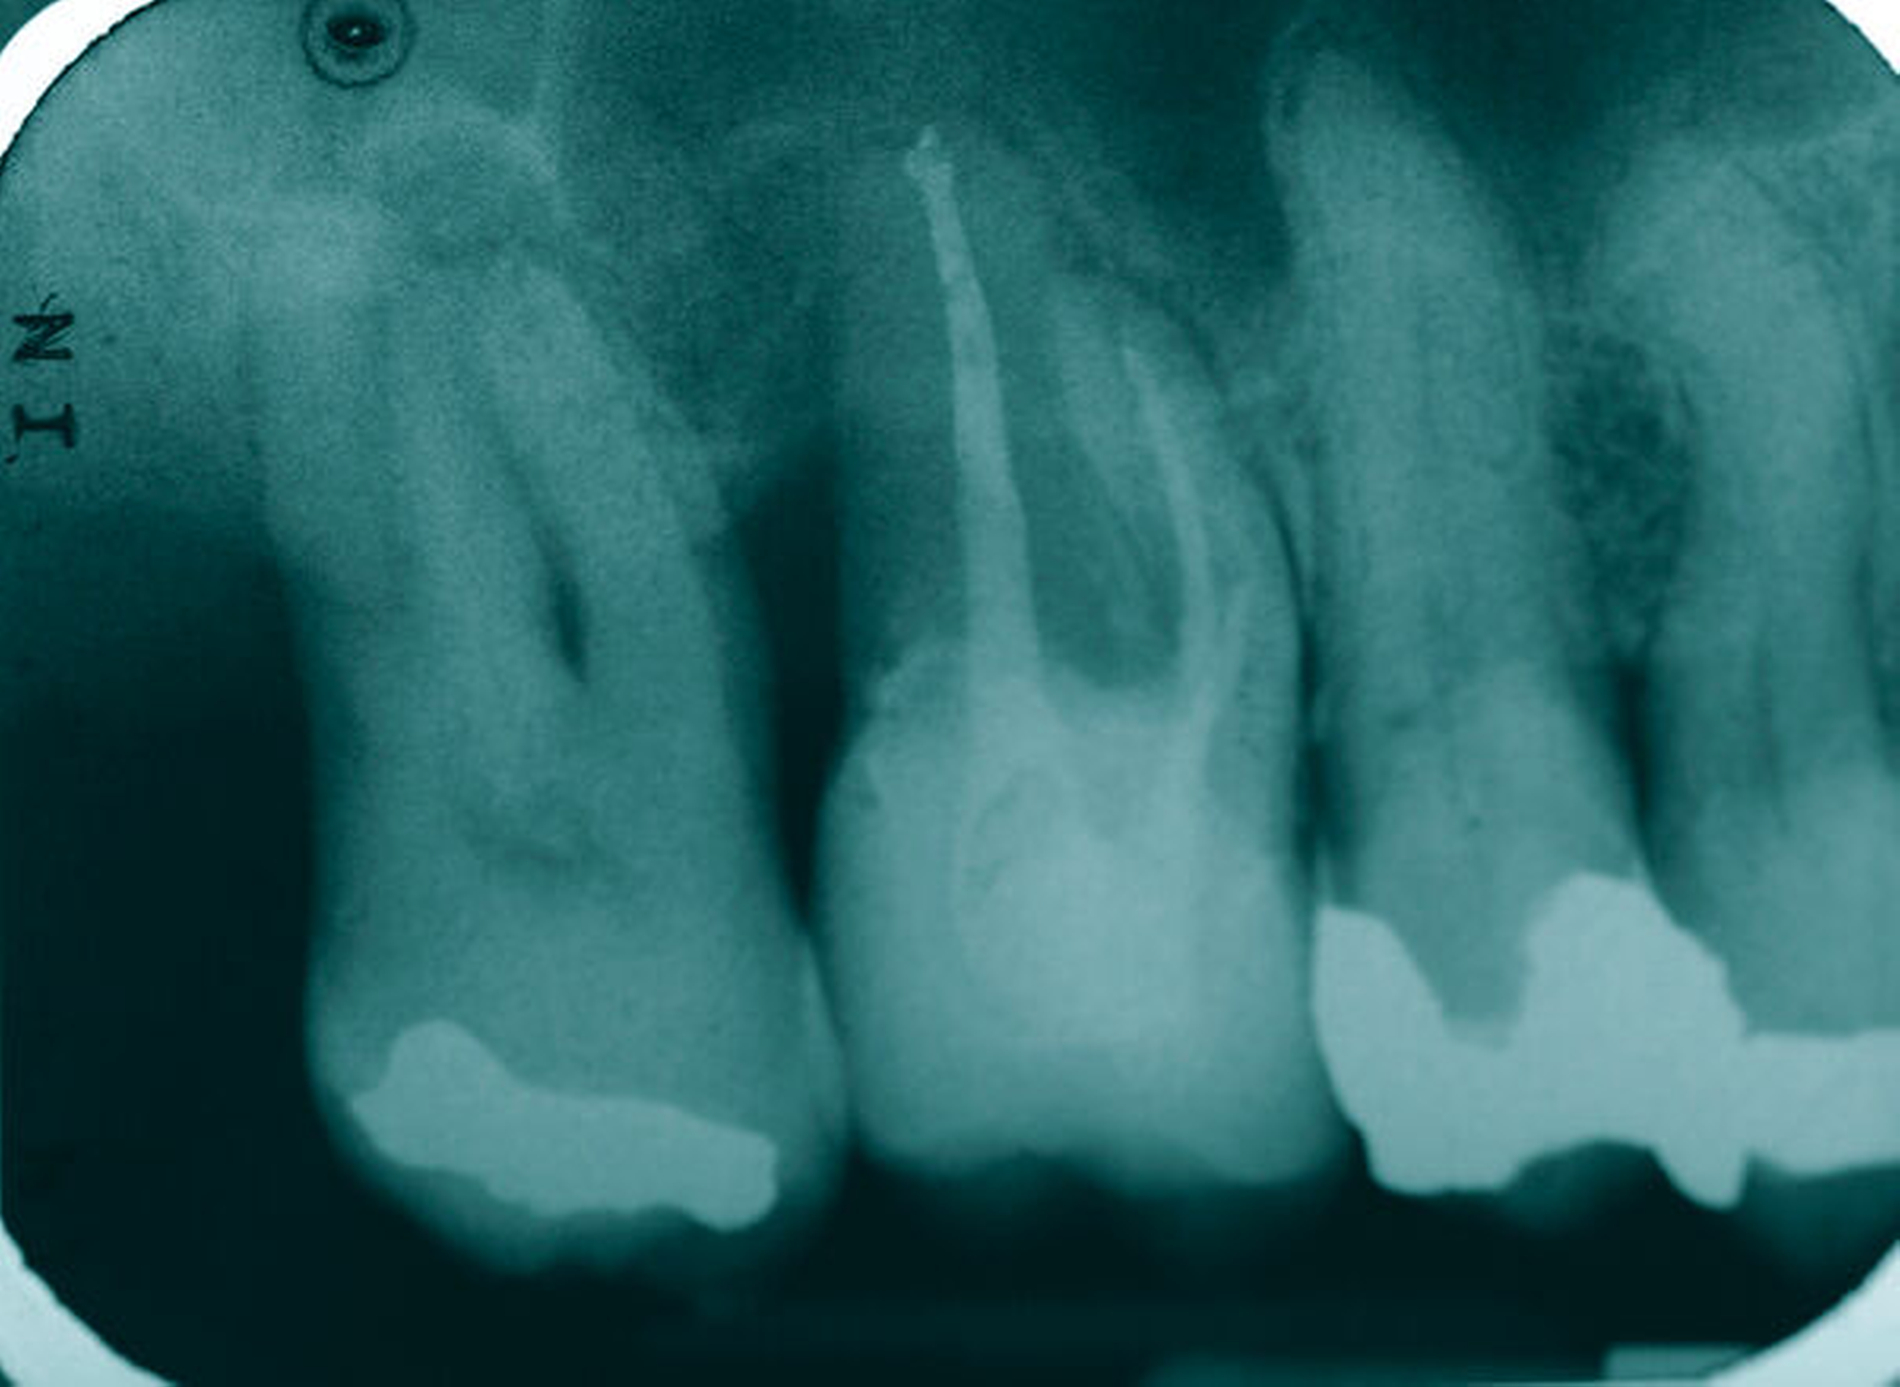

Um sicherzustellen, dass der Zahn für das gewählte Vorgehen geeignet ist, erfolgt zunächst die Auswertung der vorliegenden Röntgenbilder, eine ausführliche parodontale Sondierung des Zahnes mit Parodontalsonde und Nabers-Sonde, um Attachment und Furkationsbefall sowie möglicherweise tastbare anatomische Besonderheiten zu beurteilen. Das Röntgenbild besitzt zwar eine nur eingeschränkte Aussagekraft bezüglich des interradikulären Knochenangebots [Eickholz, 2010; Topoll et al., 1988], das durch das DVT besser beurteilbar zu sein scheint [Walter et al., 2010], jedoch waren die in diesem Beitrag gezeigten Fälle durch die Kombination aus klinischer und röntgenologischer Diagnostik ausreichend beurteilbar, um eine Therapieplanung ohne DVT durchzuführen.

Eine 46-jährige Patientin klagte 2014 über wiederkehrende Beschwerden an Zahn 16, die sich auch nach einer endodontischen Behandlung nicht besserten. Wiederholt waren submuköse Abszesse aufgetreten. Lokalisiert war die Sondierungstiefe stark erhöht, was auf eine Längsfraktur der mesiobukkalen Wurzel hindeutete. Die Patientin wurde über die Möglichkeiten der Amputation der mesiobukkalen Wurzel sowie alternativ der Extraktion des Zahnes aufgeklärt und entschied sich für den Versuch des Zahnerhalts mittels Teilamputation der mesiobukkalen Wurzel.

Eine 53-jährige Patientin stellte sich 2015 mit plötzlich aufgetretenen, starken Beschwerden an Zahn 16 und der Bitte um Abklärung vor. Es erfolgte die klinische und röntgenologische Befundung des Zahnes, der neben einer apikalen Parodontitis auch eine große, fast bis in die Furkation reichende Kronenrandkaries an der mesiobukkalen Wurzel aufwies. Um diesen vorhersagbar versorgen zu können, wurde der Patientin die endodontische Behandlung mit Amputation der mesiobukkalen Wurzel und anschließender Versorgung mittels Vollkrone als Alternative zur Extraktion aufgezeigt. Sie entschied sich für den Zahnerhalt.